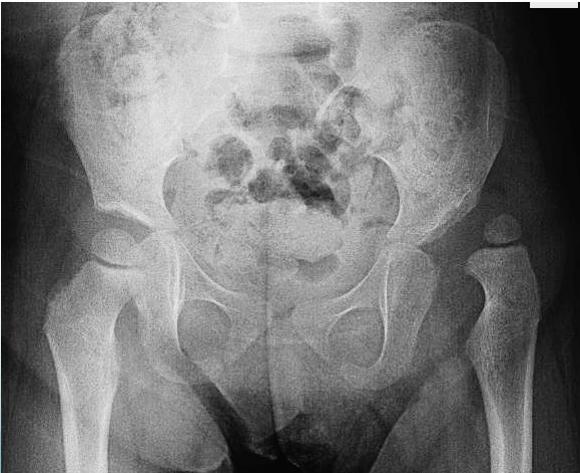

Radiology (X-ray)

Early Infancy

- Not reliable in early infancy - ultrasound is preferred

After 3 Months

- More reliable for assessment

- AP abduction view:

- Long axis of femur normally passes through acetabulum

After 6 Months

- Clearly shows dislocation

- Femoral head ossific center size and position assessment